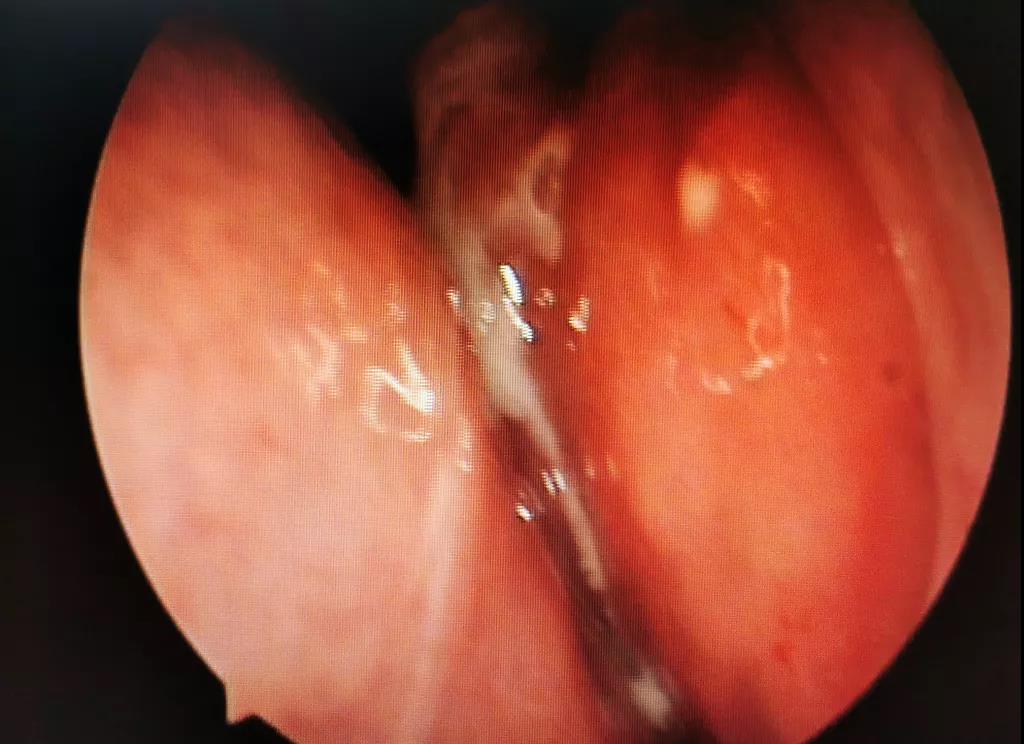

(魏大叔鼻內(nèi)鏡圖示)

通過鼻內(nèi)鏡檢查發(fā)現(xiàn),魏大叔左鼻道有半透明息肉樣新生物,表面附著黃色膿性物。

再結(jié)合魏大叔的癥狀及CT報(bào)告,黃博士高度懷疑魏大叔是真菌性鼻竇炎,建議魏大叔行手術(shù)治療。